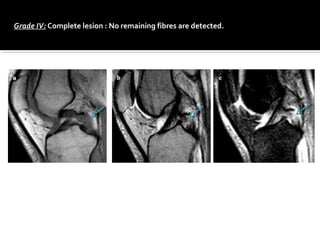

Grade IV: Complete lesion : No remaining fibres are detected.

Grade IV: Completelesion : No remaining fibres are detected.